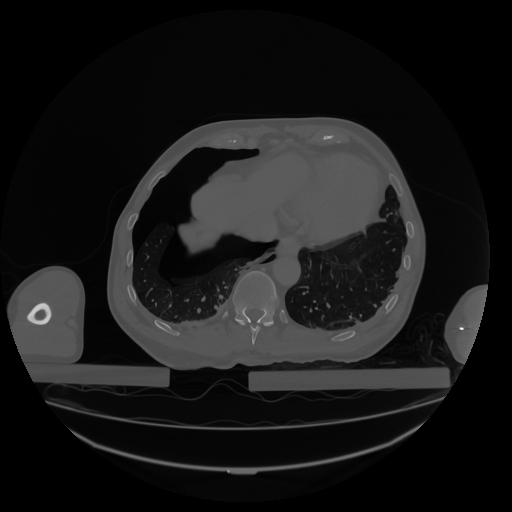

34 CUERPO,CE,Vol,1.0,CUERPO,,